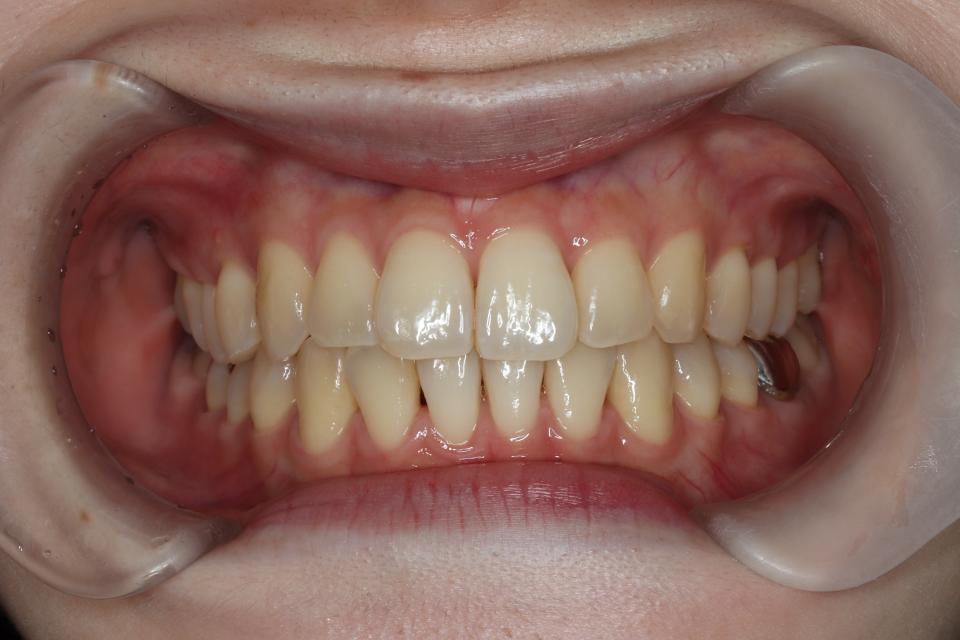

矯正治療後

歯を動かす治療は終了し、

現在は上下の前歯の裏側に後戻り防止の針金(FIX)を貼り、

定期的なチェックをしています。

| 年齢・性別 | 20代女性 |

| 矯正治療期間 | 7か月・7回(保定装置装着まで※保定観察を除きます) |

| 抜歯の有無 | なし |

| 治療費 | 670000円(検査/診断/施術料・保定装置代を含む※保定期間中は保定観察料金が別途必要です(3000円/回) ) |

| リスク・注意点 |

歯の移動に伴い痛みを感じる場合がある 治療後保定装置を使わないと後戻りを生じる |